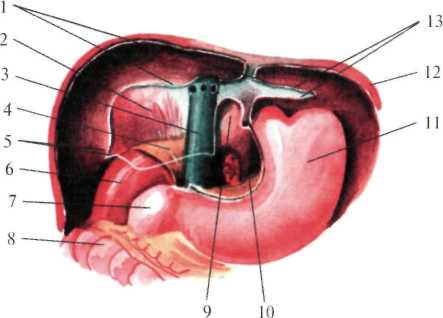

Рис.1.25. Сегменты печени

В задней части диафрагмальной поверхности печени серповидная связка, веерообразно разделившись, переходит в венечную (lig. coronarium), расположенную во фронтальной плоскости. Справа и слева венечная связка переходит в треугольную (lig. triangulare dextra et sinistra)(рис.1.26). При переходе висцеральной брюшины с печени на соседние органы образуются печеночно-желудочная и печеночно-дуоденальная связки, а также печеночно-почечная связка (lig. hepatorenale), расположенная между нижней поверхностью печени и правой почкой.

Рис.1.26. Ложе печени (по Неттеру, с изменениями).

1 — lig. coronarium; 2 — area nuda; 3 — v. cava inferior; 4 — gl. suprarenalis; 5 — lig. triangulare dextrum;

6 — ren; 7 — duodenum; 8 — colon transversum; 9 — recessus superior; 10 — bursa omentalis; 11 — gaster;

12 — diaphragma; 13 — lig. triangulare sinistrum.